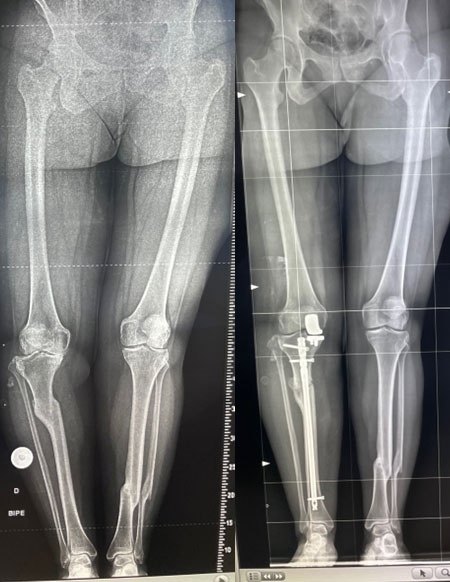

Management of a post-traumatic knee pain: Post-op XRays

Intra-operative images